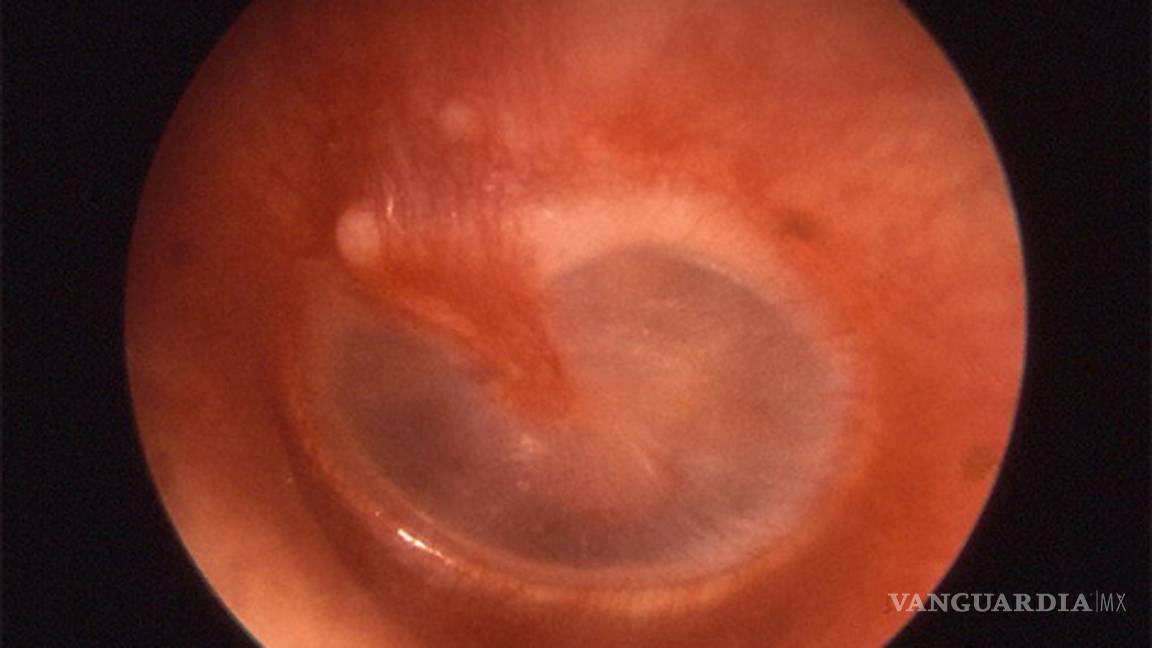

Rodríguez Weber comentó que el diagnóstico se realiza ante la inspección del médico con el otoscopio, instrumento con un haz de luz que ayuda a visualizar, examinar la condición del canal auditivo y determinar si hay inflamación en la membrana timpánica.